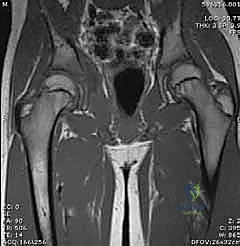

- الرنين المغناطيسي (MRI): يتم اللجوء إليه إذا كان هناك اشتباه في وجود التهاب عظم ونقي (Osteomyelitis) مصاحب، أو خراج في العضلات المحيطة، ولكنه يتطلب تزليج الطفل (تخدير) ويستغرق وقتاً.